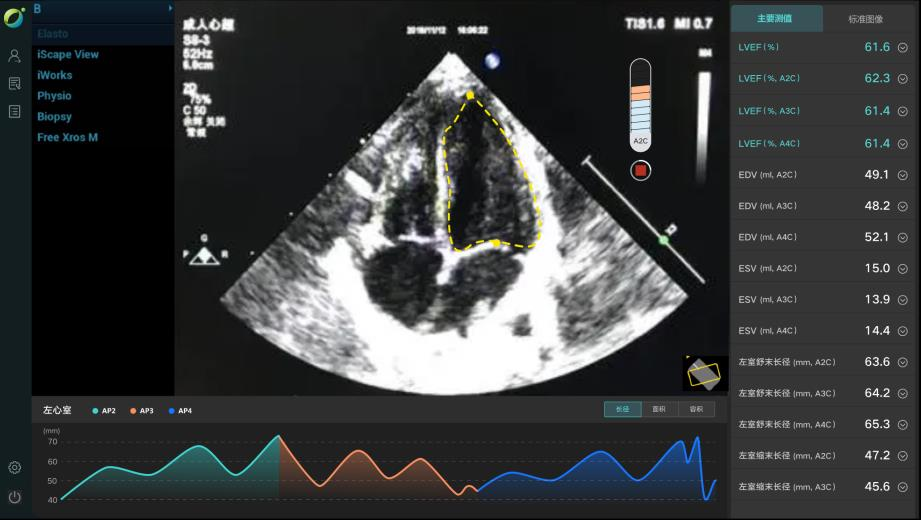

AI智能影像輔助診斷技術(shù)具有對醫(yī)學(xué)影像進(jìn)行圖像篩查、病灶分類、定位、檢測、圖像分割等優(yōu)勢。它能夠在海量的醫(yī)學(xué)影像中準(zhǔn)確、快速且客觀地篩選出特定疾病的影像,確定圖像中病變區(qū)域的空間位置,檢測需要識別圖像中所有的目標(biāo)并且確定其類別,并在醫(yī)學(xué)影像中分割標(biāo)注出不同的組織和器官,計(jì)算圖像中的血流量等代謝信息。

除上述肺結(jié)節(jié)人工智能篩查示例外,目前已形成了全鏈路人工智能產(chǎn)品解決方案,在影像、超聲、病理方面都與AI智能影像輔助診斷技術(shù)高效結(jié)合,幫助醫(yī)院實(shí)現(xiàn)自動化、高精度的影像診斷檢查,讓患者在疾病篩查中實(shí)現(xiàn)早期診斷、預(yù)測、治療、療效評估與監(jiān)測。